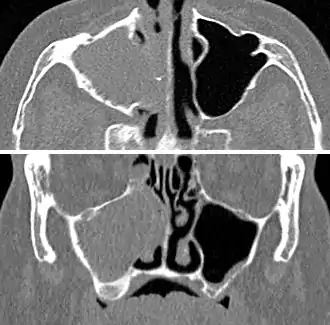

A CT scan showing sinusitis of the ethmoid sinus

For sinusitis lasting more than 12 weeks, a CT scan is recommended.[54] On a CT scan, acute sinus secretions have a radiodensity of 10 to 25 Hounsfield units (HU), but in a more chronic state they become more viscous, with a radiodensity of 30 to 60 HU.[56]